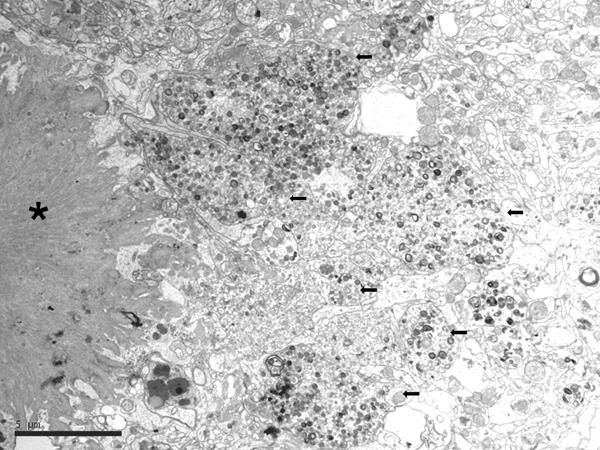

Electron microscopic studies revealed that NFTs were composed of paired helical filaments (PHFs) that disrupted the architecture of the cyto-skeleton. SPs were forged from a core of compact fibrils consistent with amyloids surrounded by dystrophic neurites filled with altered mitochondria, vesicles, numerous pleomorphic residual bodies, and PHFs (56-61) (Figure 3).

Figure 3: Electron microscopy of an SP showing the central core of amyloid fibrils (asterisk) and peripheral dystrophic neurites (black arrows) filled with vesicles, dense bodies, abnormal mitochondria, and paired helical filaments; bar = 5μm.